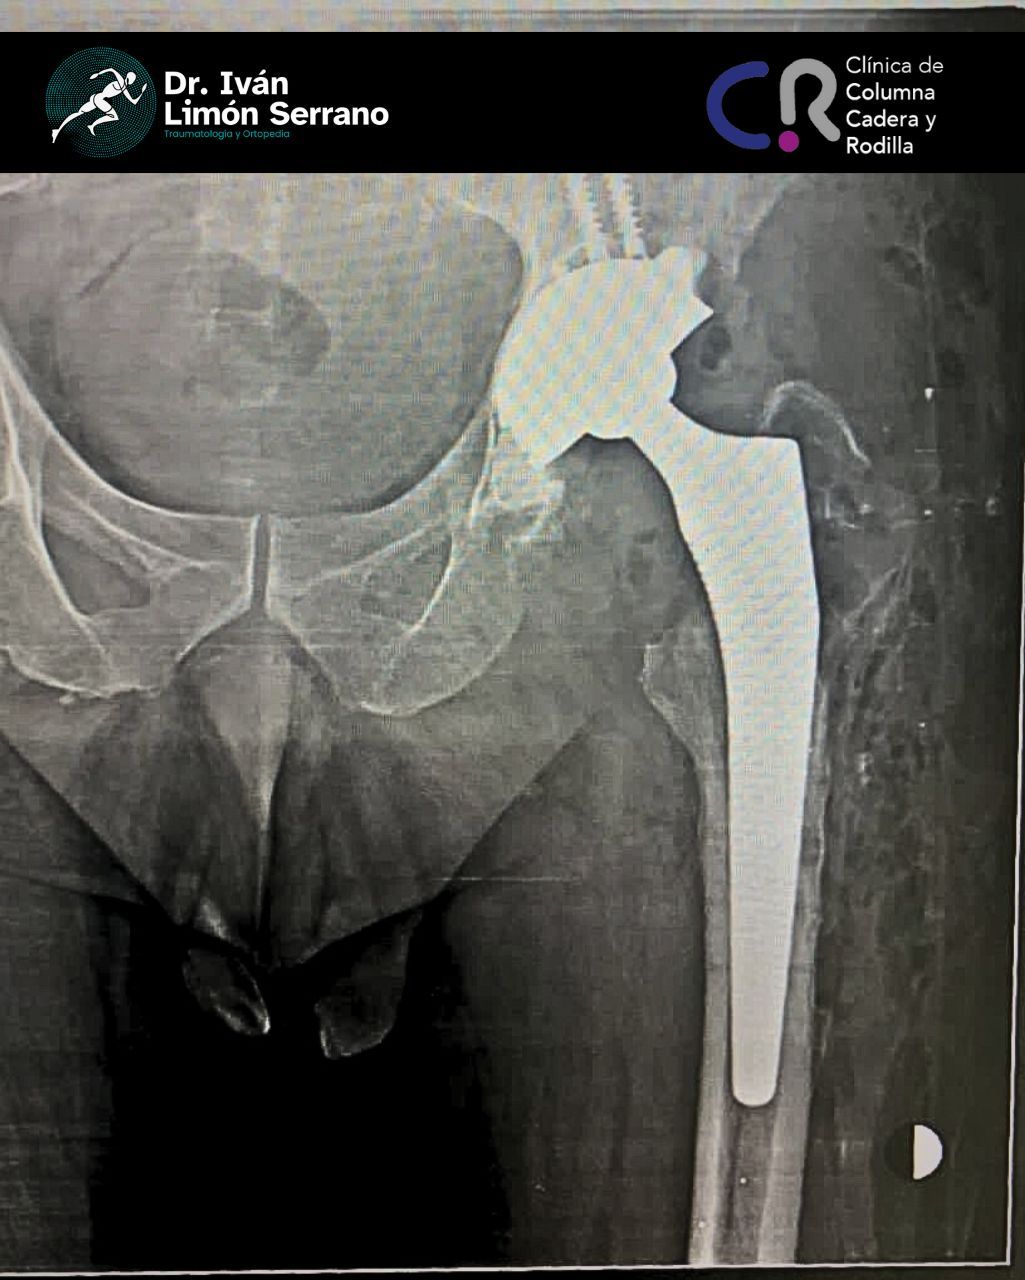

• Prótesis de cadera

• Cirugía cadera

• Artroscopia de cadera

Es una enfermedad articular caracterizada por la por degeneración, perdida del cartílago y alteración del hueso subcondral asociado a cambios en tejidos blandos. Se caracteriza por dolor articular, limitación funcional, crepitación y grados variables de inflamación. Factores de riego como sobrepeso, obesidad, debilidad muscular, actividad física pesada traumatismos, edad avanzada, sexo femenino, factores genéticos, trastornos metabólicos y congénito. Actualmente existen tratamientos desde lo no farmacológico control de peso hasta el tratamiento quirúrgico como lo es el reemplazo articular mediante la colocación de prótesis total.